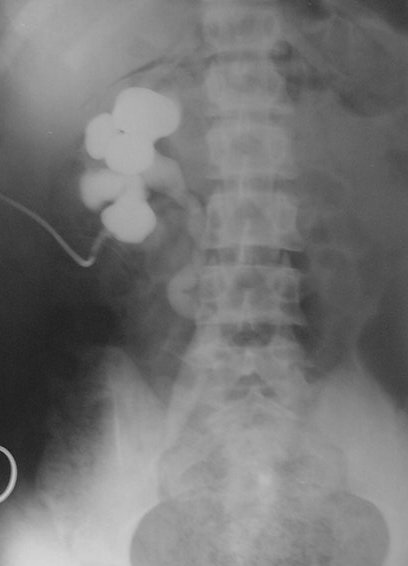

Hidronefroză stângă, sondă ureterală double J